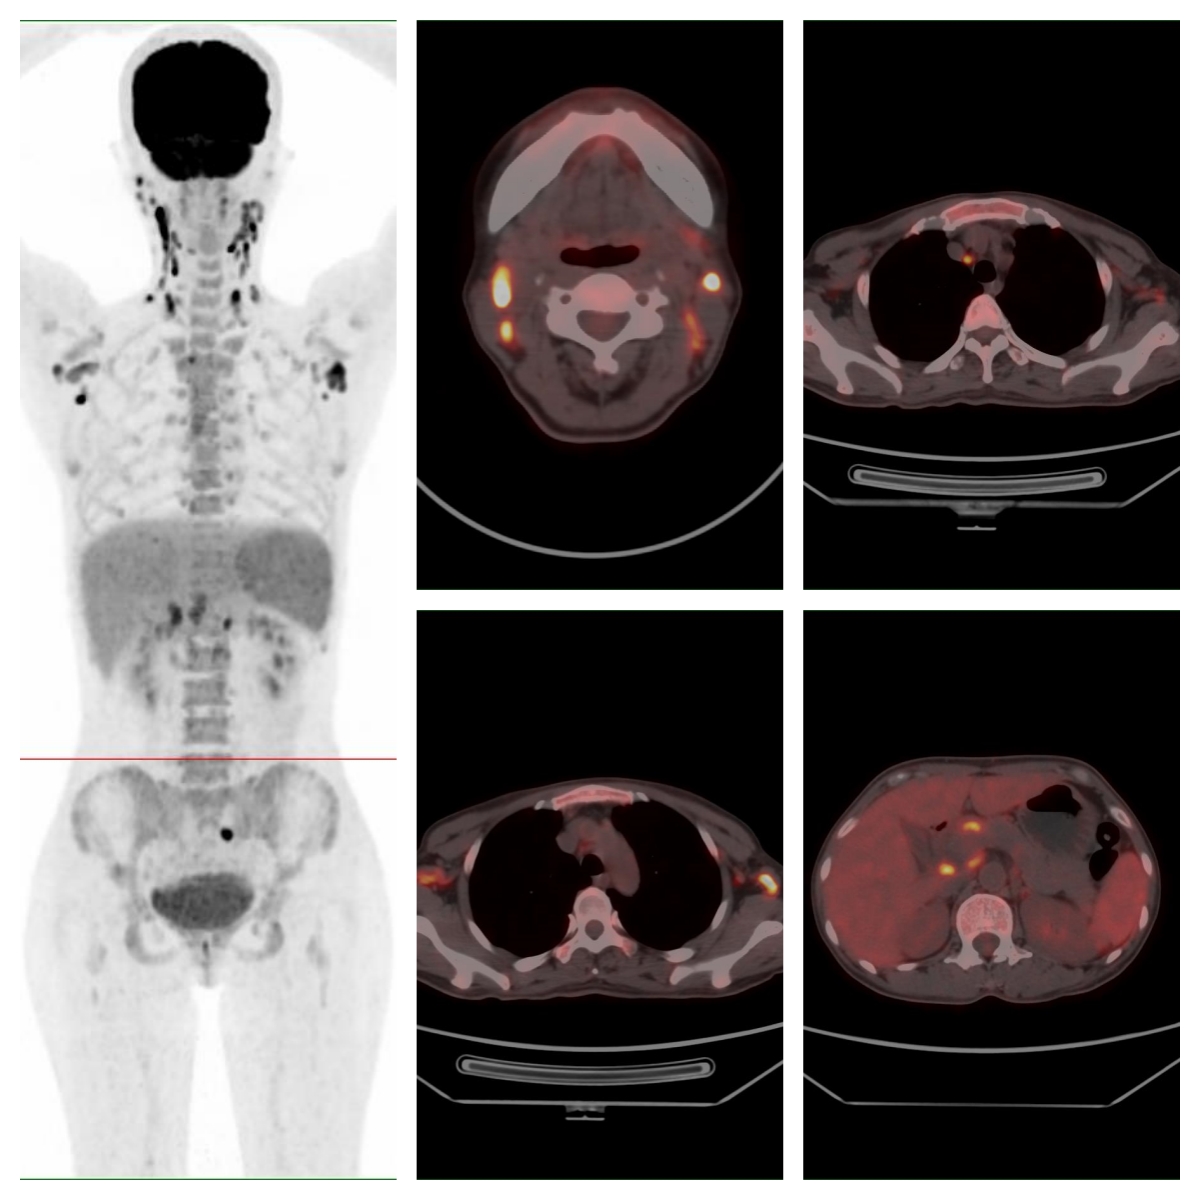

為明確病情,完善PET/CT檢查

PET/CT示全身多處淋巴結(jié)、多處骨骼及脾臟代謝異常,考慮系統(tǒng)性疾?。▓D示);顯像劑攝取最高者位于右側(cè)頸部Ⅱ區(qū),SUVmax約19.6。

圖 全身多處淋巴結(jié)、骨骼及脾臟代謝異常。

經(jīng)多學(xué)科會診,對右側(cè)頸部代謝最高的淋巴結(jié)進(jìn)行了完整切除活檢,病理示外周T細(xì)胞淋巴瘤-非特指型。